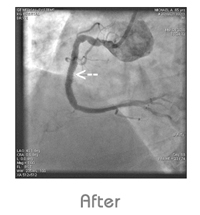

Coronary Angioplasty

A special catheter with small balloon at the tip is used to open up the diseased artery without entailing actual surgery.